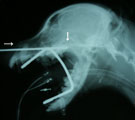

鼻に何かが突っかかった様子あり 内視鏡にて後鼻孔に白い異物がみえた(画面右) 長い鉗子を外鼻孔よりいれても左右とも途中(↓)で止まる 内視鏡で後鼻孔に鉗子を挿入しても左右とも詰まる(↓)

経過:来院時、粘漿性鼻汁あり、ときおり軽く首をのばして動きがとまり鼻に何かが詰まったようになる様子あり。動脈血酸素分圧は93.6 mmHgで正常。人前では元気にはしゃぎまわるが夜間鼻詰まり症状で熟睡できないようであった。内視鏡検査で鼻道は狭くなり白い異物が観察された。両側の外鼻孔よりやわらかいチューブをいれても奥で通らず、長い鉗子をいれても詰まった。内視鏡の鉗子を後鼻孔に挿入したがそれでも同じところの両側が詰まっていた。異物が強く陥入もしくは鼻腔内骨折が疑われたので、飼主様に説明後外科的に整復することにした。術中、後者であることが判明。骨片を除去し両側の鼻道が貫通した。しかし、その処置直後突然心停止した。ただちに蘇生処置を施し一時心拍が再開したが再度心停止し救命しえなかった。